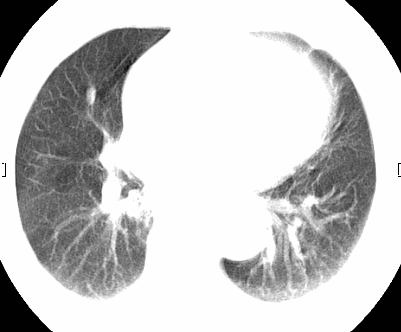

标题: CT26680:肺部右下肺静脉干结节的界定 [打印本页]

标题: CT26680:肺部右下肺静脉干结节的界定

经追查说有支扩咯血病史,但不确定

考虑1、周围型肺癌,2肺静脉畸形,前者可能大,建议增强检查。

不除外淋巴结肿大。

考虑1、周围型肺癌,2肺静脉畸形,前者可能大,建议增强检查。支持!

不排除右肺下叶周围型肺癌可能。